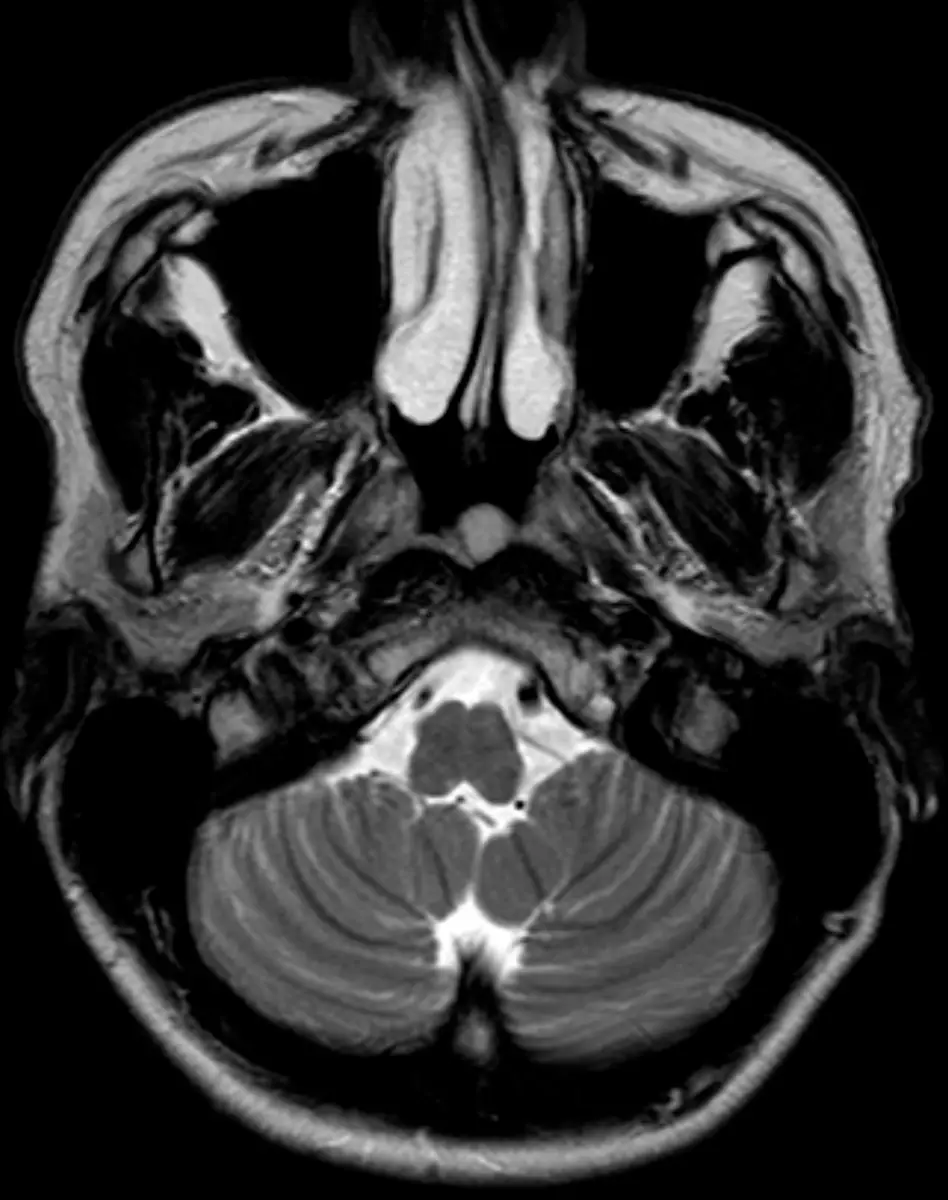

МРТ придаточных пазух носа

Визуализация носовой полости и придаточных пазух носа.